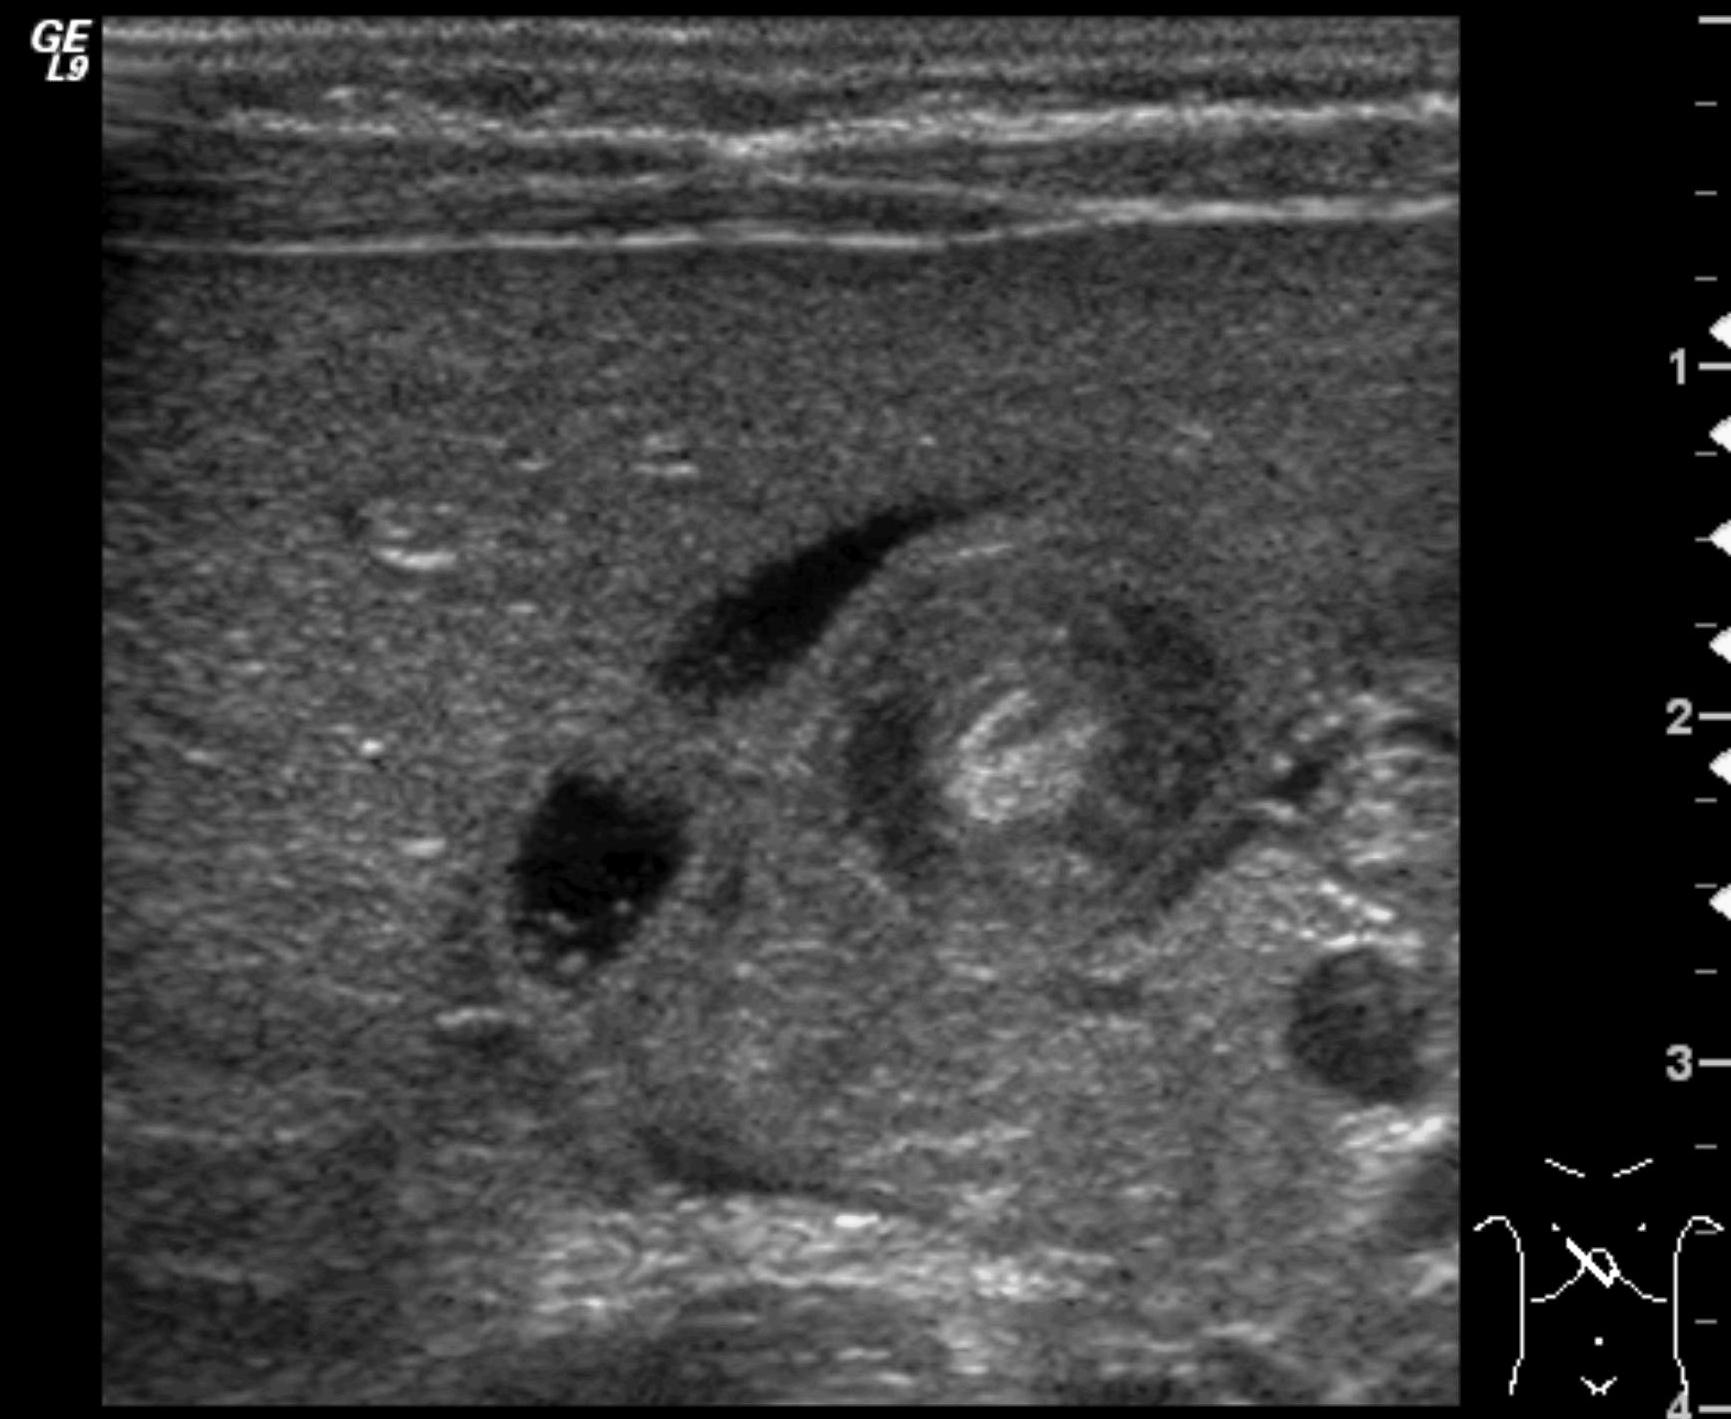

Invagination. A distal intestinal loop invaginating to a proximal intestinal loop can result in a mechanical intestinal obstruction, and cause ischemic damage. It most frequently occurs in infants (3-24 months) with recurring, colic-like complaints, distended intestines, a palpable mass and with frequent vomiting and bloody stool. Invagination requires immediate diagnosis and desinvagination. US exam reveals the invaginated intestines as a “target” sign in axial cross section and looks like a “pseudokidney” in longitudinal cross section. The therapy is hydrostatic or pneumatic desinvagination. Perforation and/or peritonitis are absolute contraindications to these procedures. Hydrostatic desinvagination can be performed under fluoroscopy or with US guidance and is considered successful if air or the contrast material appears in the terminal ileum and the invaginated loop disappears. If these efforts do not succeed, surgical desinvagination is needed.

17. “Target” sign. Invagination. .